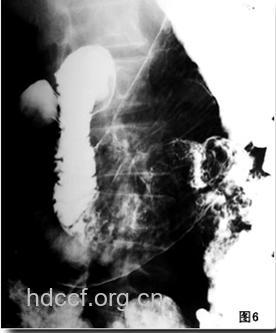

1、龛影为溃疡病的直接征象。切线位,龛影凸出于胃内壁轮廓之处,呈乳头状或半圆形;正位,龛影为圆形或椭圆形,其边缘光滑整齐。

2、龛影周围粘膜纹:切线位,龛影与胃交界处显示1~2mm的透明细线影,见于龛影的上缘或下缘,或龛影的整个边缘。

3、“狭颈征”:切线位,龛影口部与胃腔交界处有约0。5~1cm一段狭于龛影的口径,称为“狭颈征”。

4、“项圈征”:治疗胃溃疡最好的药在龛影口部有一边缘光滑细线状密度减低区,如颈部戴的项圈。

5、龛影周围的“日晕征”:正位,龛影周围有宽窄不一致的透亮带,边缘光滑。

6、以龛影为中心的粘膜皱襞纠集;呈放射状分布,其外围逐渐变细消失,为慢性溃疡的另一征象。

(1)胃大弯侧指状切迹;(2)胃小弯侧缩短;(3)胃角切迹增宽;(4)幽门管狭窄性梗阻,胃内滞留液。